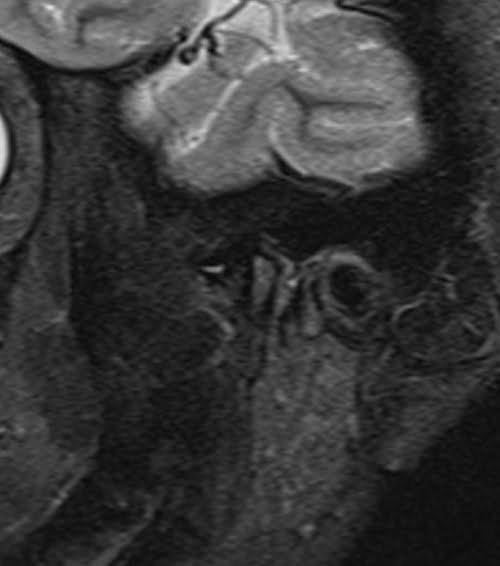

TMJ left side STIR images